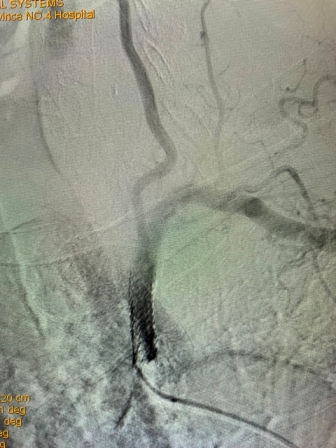

2021年8月5日,亚色视频 神经内科神经介入专家团队成功完成首例锁骨下动脉再通介入术

(术前造影) (术后再通造影)